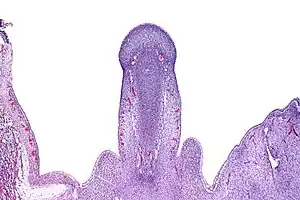

Micrograph of the primordial phallus, H&E stain.